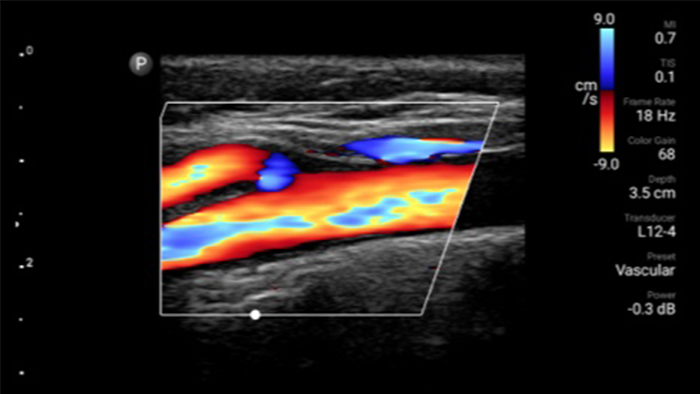

Decrease complications of CVC insertions

Real-time ultrasound guidance can improve the accuracy and safety of CVC insertions.

Lumify L12-4 broadband linear array transducer

• 12 to 4 MHz extended operating frequency range • Aperture size: 34mm • 2D, steerable color Doppler, M-mode, advanced XRES and multivariate harmonic imaging, SonoCT • High resolution imaging for shallow applications: soft tissue, vascular, superficial, musculoskeletal, and lung • Center line marker • USB-C transducer with replaceable cable